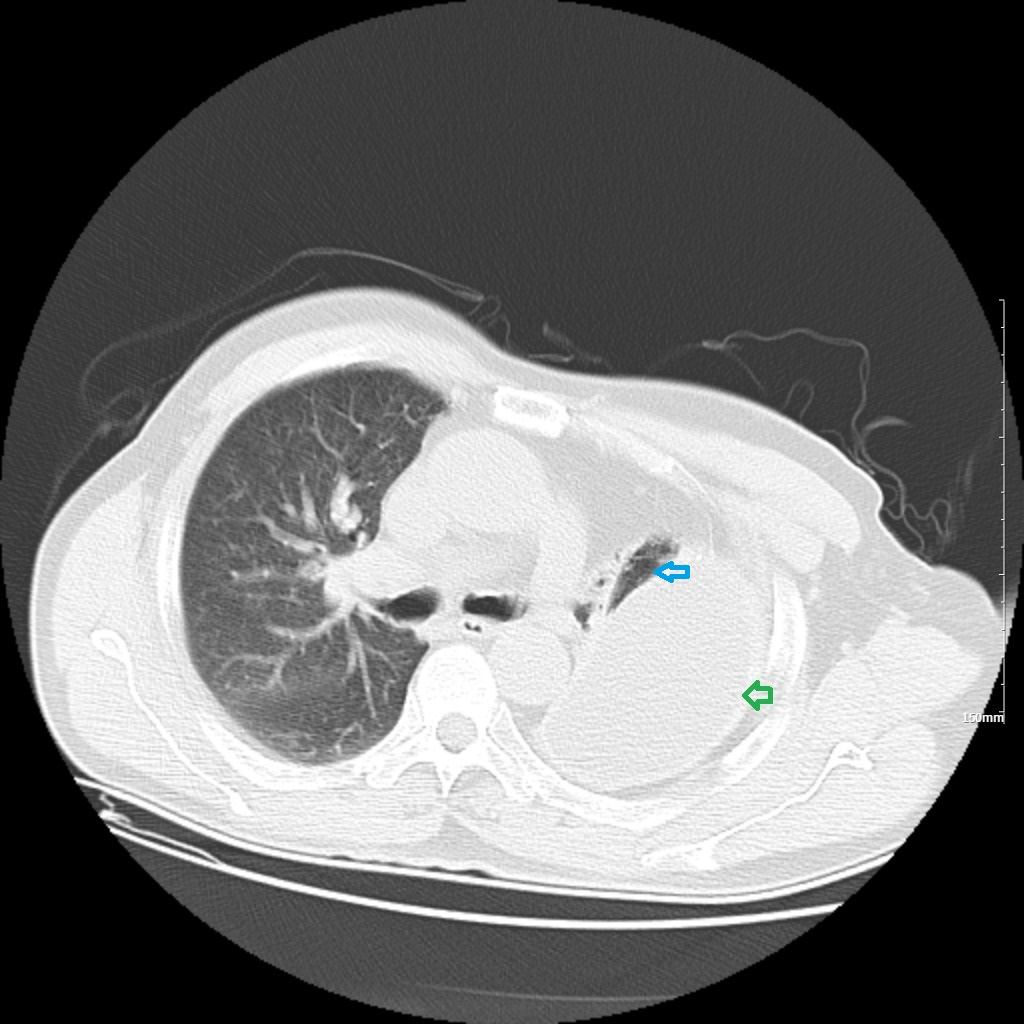

胸部CT示两肺及肋骨平扫未见明显挫伤征象,左侧胸腔包裹性积液并胸膜增厚、钙化,左肺不张(见图1-图4)。

2. 绿色箭头:左侧胸腔积液;蓝色箭头:左肺压迫性肺不张。